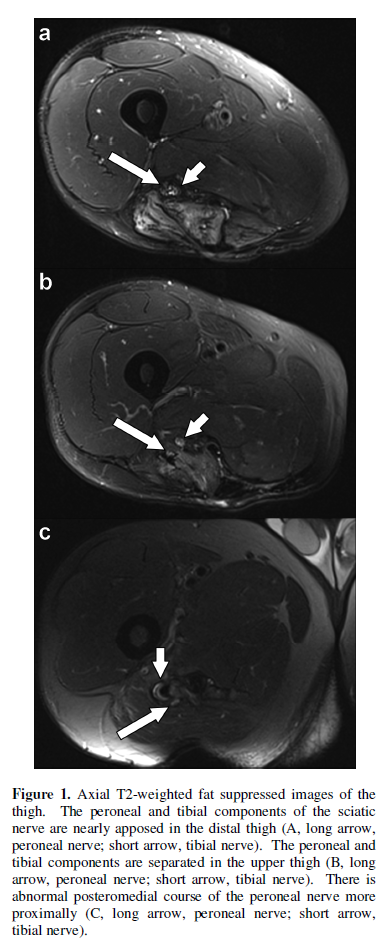

semitendinosus. MR neurography was performed on a 3T MRI scanner (MAGNETOM

Skyra, Siemens, Erlangen, Germany). It demonstrated abnormal separation of the

peroneal and tibial components of the sciatic nerve in the proximal thigh over

a distance of approximately 8 cm (Figure

1a, 1b). The peroneal component demonstrated an unusual course

posteromedial to the tibial component and appeared to terminate in the region

of the ischial tuberosity (Figure 1c).